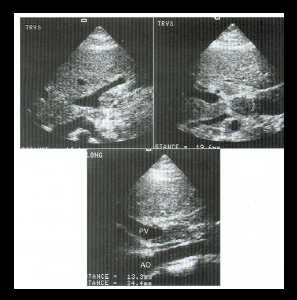

what do you see int he top lt image?

mass effect

what are these examples of?

retroperitoneal lymph nodes